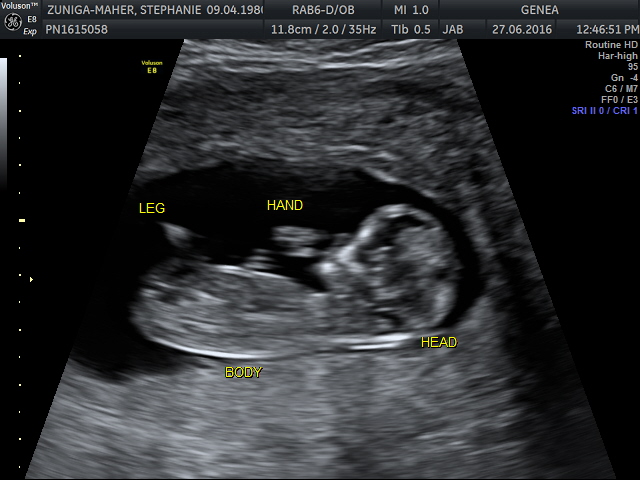

Actually has nothing to do with cooking or triathlons, but it promises to be life changing…. And it’s due to arrive in January 2017.

We’re obviously thrilled to welcome our new little cook/triathlete into the world and really excited to share our newest project with you!

I think if you look closely, it’s already practicing cycling in the video- and yes, it’s a bit alien like at the moment, but we fully expect him (or her) to only get cuter from here!

BABY 12 WEEKS_17 labelled